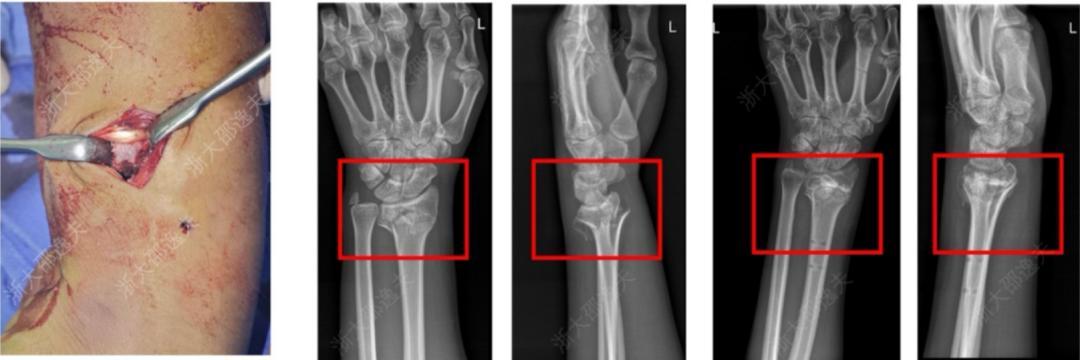

它在多家醫院150餘例受試病例中展現出了良好的安全性和有效性,各項指標達到預設標準。其中一位年輕工人因外傷致腕部粉碎性骨折,爲避免傳統的鋼板內固定手術方案,醫生通過一個2-3釐米的微創切口注入了“骨02”,便黏合了碎骨。術後複查顯示,患者骨折癒合良好,手腕功能得以恢復。